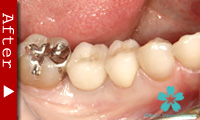

歯を一本だけ失った場合

“失われた1本の歯根の代理品”としてインプラントを1本だけ使って失った歯の部分を修復する方法は、最も洗練された治療方法であり、審美的にも満足のいく結果が得られます。

1本のインプラントによってあたかも自分の天然歯のように自然に感じられます。顎骨の”萎縮”の心配もなく、本来の骨量を維持できます。

ブリッジを入れる時のように、健康な隣の歯を削る必要がありません。